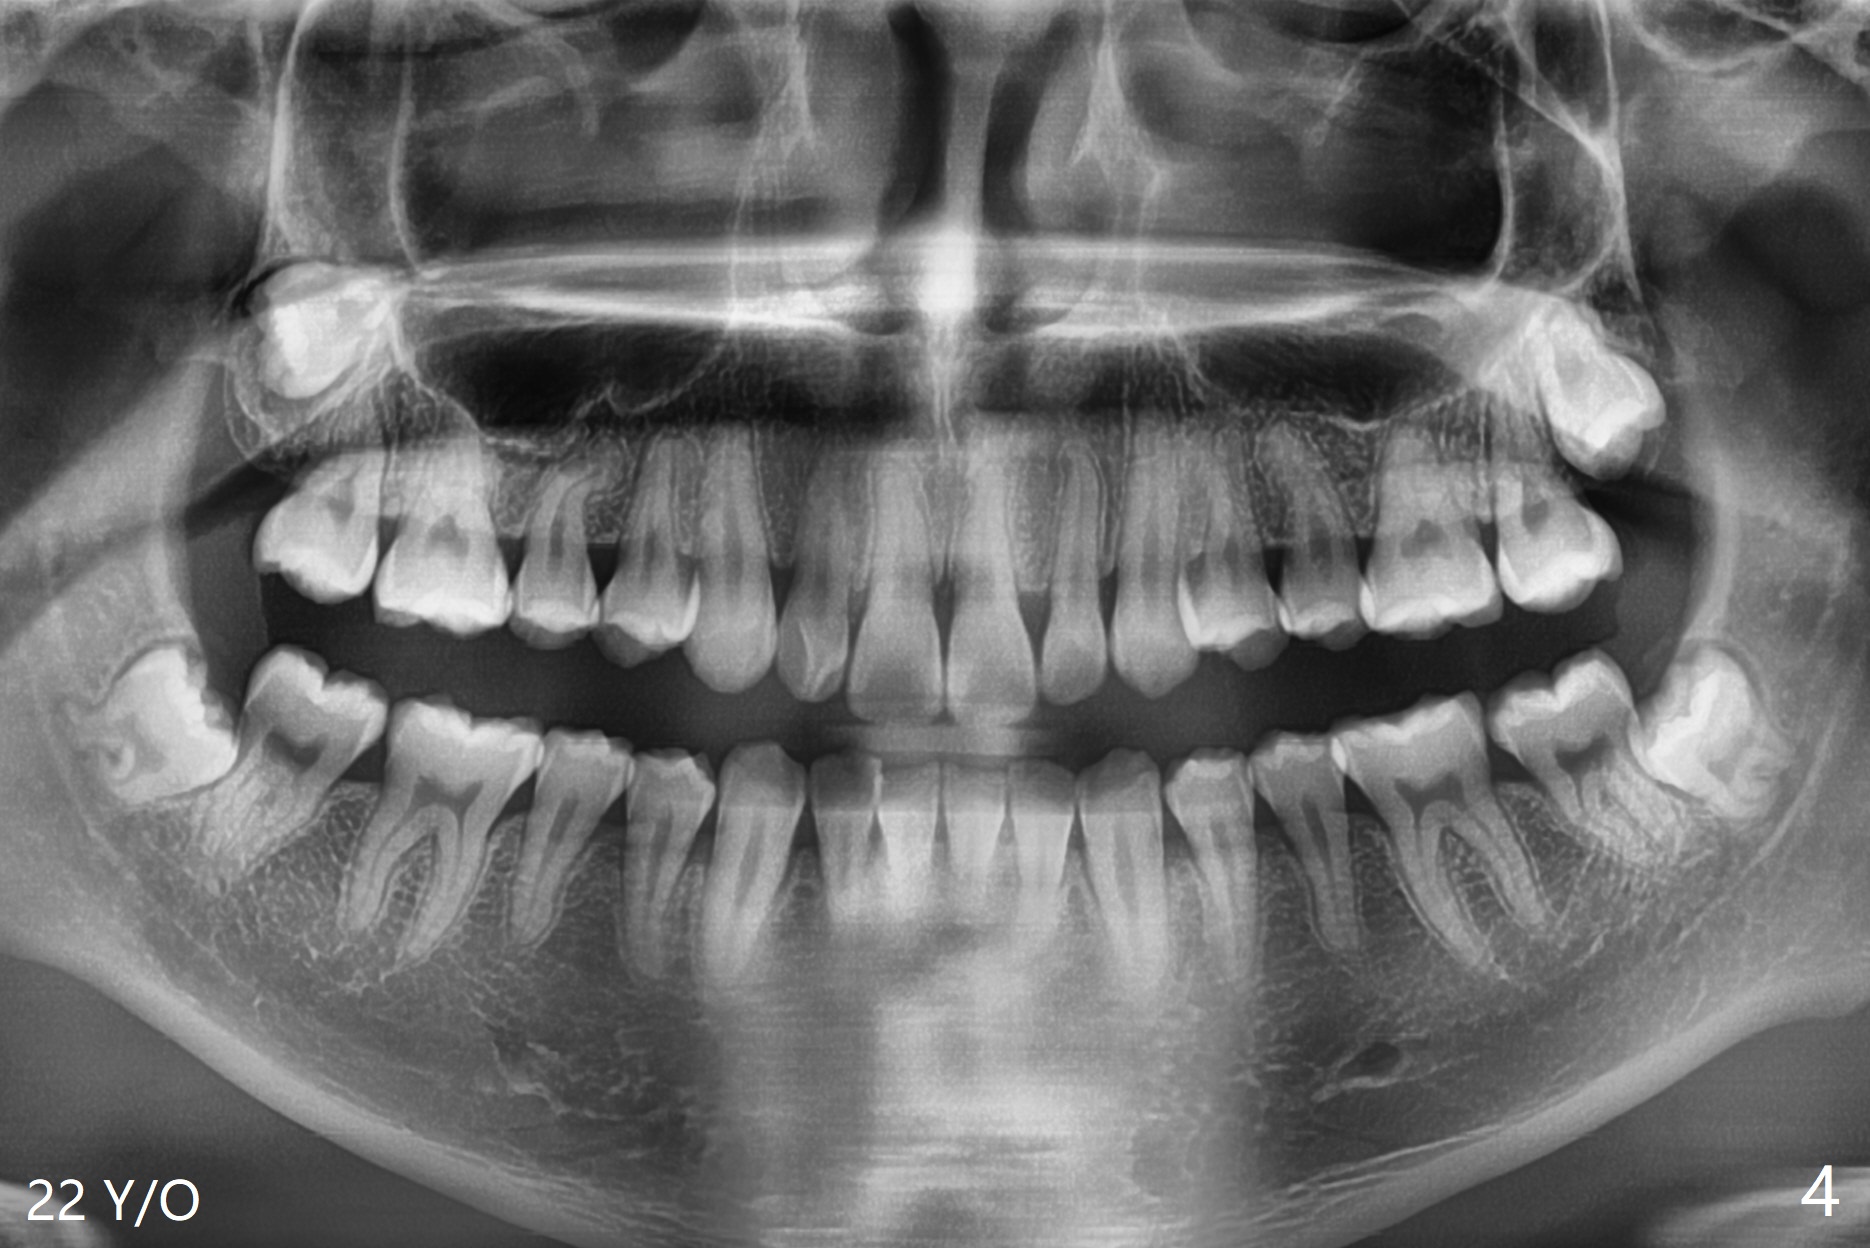

A 22-year-old man will return for 3rd molar extraction (4 of them, Fig.1-4). Prepare 2 or 3 #15 blades and 1-2 extra surgical burs. Since the third molars may overlap with the second ones, oblique incision (red line in Fig.4') will be mesial. Place Collagen and Osteogen plugs in the #32 and 17 sockets, respectively (Fig.4': C, O). As the roots are short and bone formation distal to the 2nd molars is critical, the plugs will be placed horizontally and coronally (Fig.4' white outline). No dovetail is needed. Pan 4 BW will be taken immediately and 3-4 months postop. The experiment will confirm whether collagen plug is enough to facilitate socket bone healing. In fact extraction of #1 turns out to be extremely difficult. There is not enough time for #16 and 17 extraction in one appointment (Fig.5).